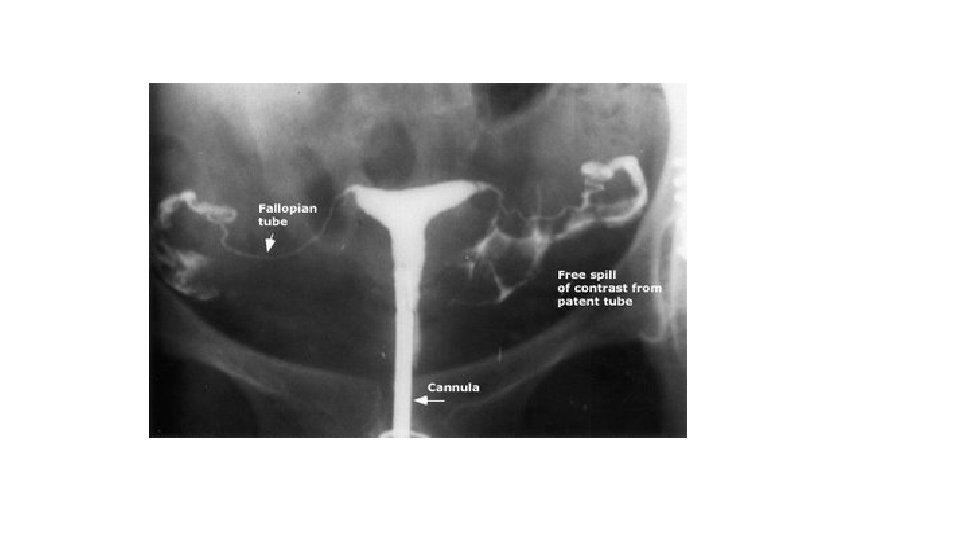

Chronic PID - Chronic inflammation may result in occlusion of one or both ends of the tube, accumulation of fluid within the tubal lumen, tubal distension serous fluid hydrosalpinx purulent fluid pyosalpinx - Healing of the inflamed pelvic structures will result in adhesion formation mainly posterior to the uterus. These adhesions may be: mild severe

Chronic PID Investigations: . Pelvic ultrasound fixed RVF uterus, cystic pelvic mass . HSG tubal obstruction, hydrosalpinx . D laparoscopy pelvic adhesions (frozen pelvis) pelvic mass